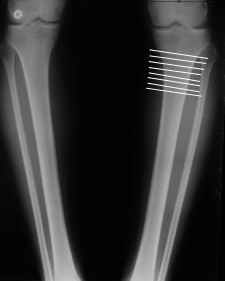

Судя по снимку у девушки имеется внутренняя установка надколенников...

Как у нее с торсионным статусом? Бедро? Голень? КТ? Торсиометры? А то, куда будут

смотреть надколенники после вашей коррекции - тоже существенный

косметический момент. Или не так?

Клинически глядел - вроде нету большой торсии.

AVM> Судя по снимку у девушки имеется внутренняя установка надколенников...

AVM> Как у нее с торсионным статусом? Бедро? Голень? КТ? Торсиометры?

Похоже, немного есть. Думаю пренебречь.

Мне представляется оптимальным на уровне 3-4 линии (т.е. как раз посредине отмеченной зоны). Если рассчимтываешь делать медиализацию, то параллельно суставной поверхности, иначе просто не сдвинешь без джистракции - отломки зацепятся. Если без медиализации - то вообще не имеет значения.